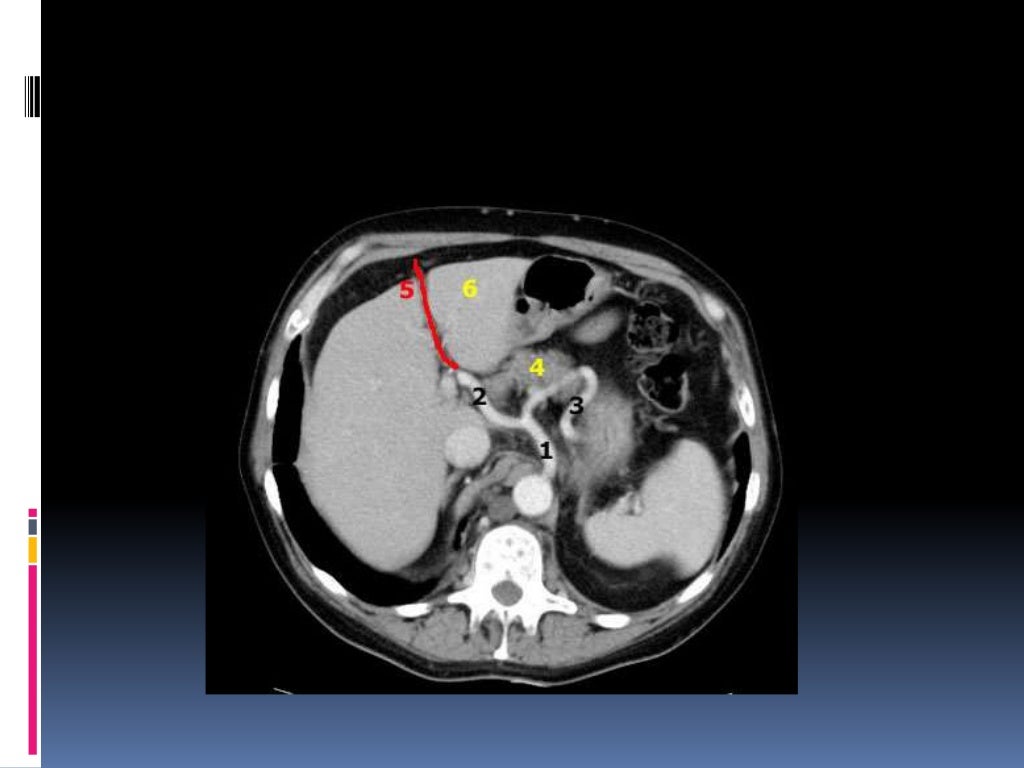

Segmentación Hepática. Breve Repaso en TC.

Apunte Cortes axiales de abdomen con tomografías Anatomía Medicina